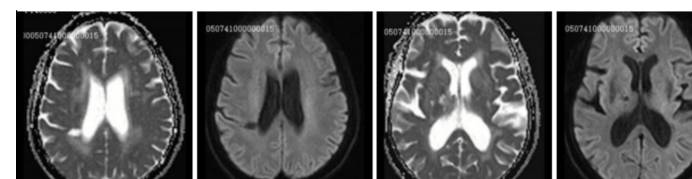

女性,62岁,智能下降2年,寡言少语、表情淡漠2天。近记忆力下降为主,缓慢加重,生活能自理,查体:P113次/分,BP173/113mmHg,可见记忆力、计算力下降,余未见异常。检验结果提示轻度贫血、血钾稍低。患者入院前MRI如下:

脑寄生虫病、低灌注脑梗死、基底动脉尖综合征丨3分钟读片 ...